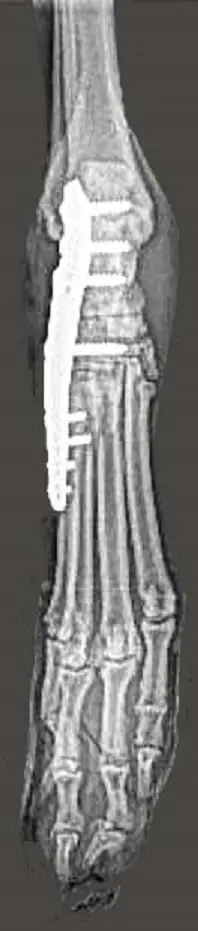

This was taken only 5 days after his operation.

Zach was having a great summer; daily walks through the woods and running around with Charlie. This all ended abruptly when Zach seriously injured his back-right leg. An Orthopedic surgeon was consulted. He said shelties are prone to this type of injury. As soon as he heard that Zach was a sheltie, he knew the injury was one of 2 things. Unfortunately, it’s the more serious injury which will require extensive surgery to rebuild his ankle. Zach doesn’t appear to be in any pain. The vet calls him stoic. Zach hops around on 3 legs. The surgery was very successful (see x-ray).